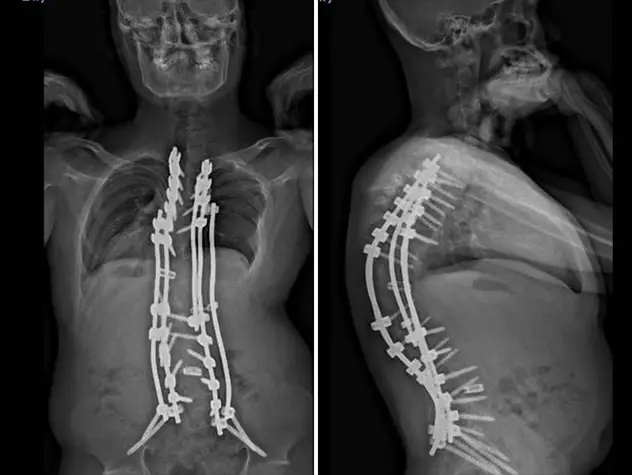

- Spine deformities: scoliosis and kyphosis, with a special focus on early-onset scoliosis.

- Specialized scoliosis treatment. Our pediatric orthopedic surgeons perform more spine surgeries than any other hospital in New York and are skilled in performing pediatric spinal surgeries. For early-onset scoliosis in children, we focus on noninvasive treatment approaches.